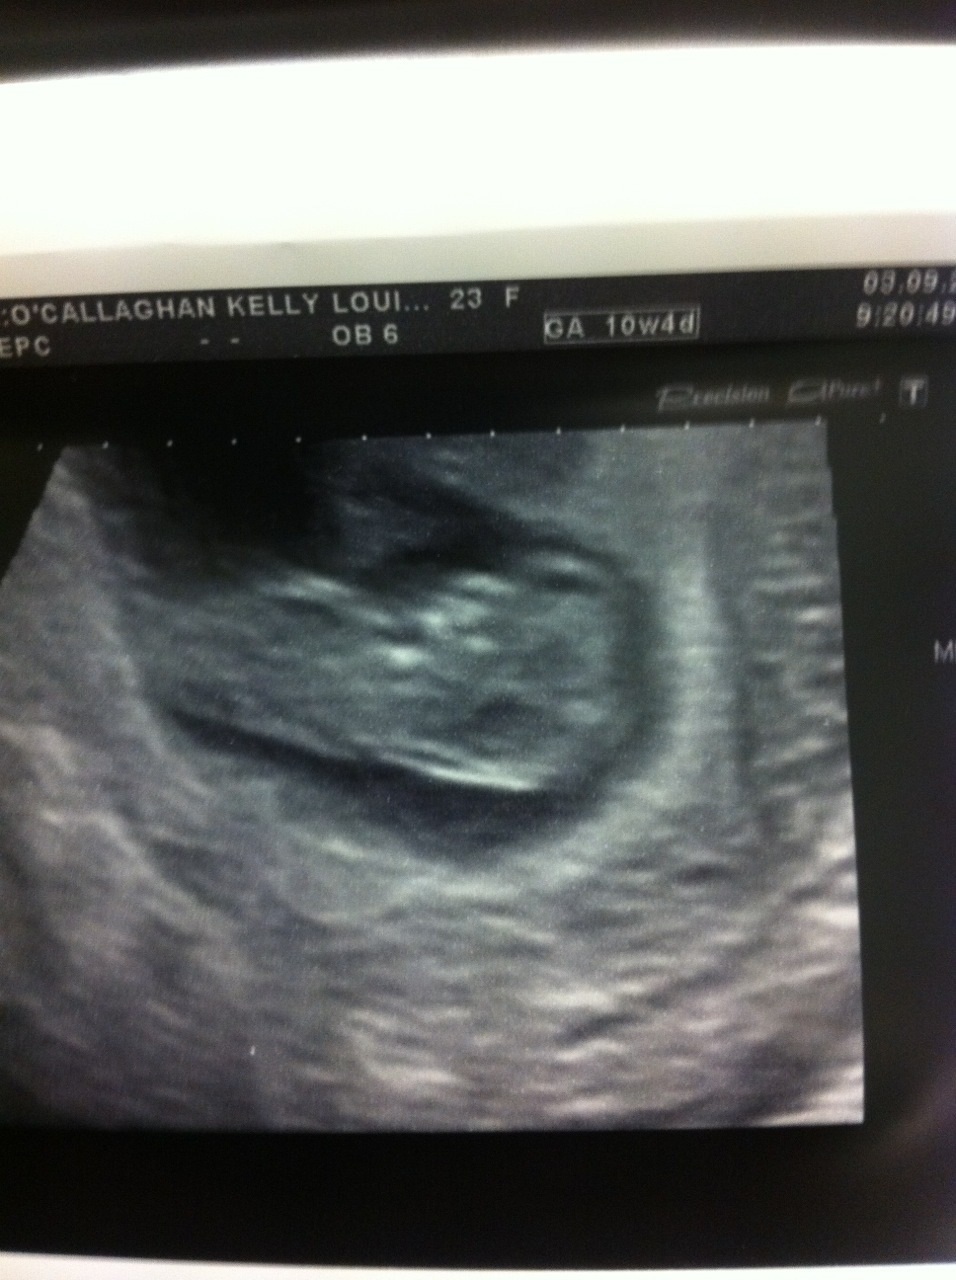

Attachment 13733